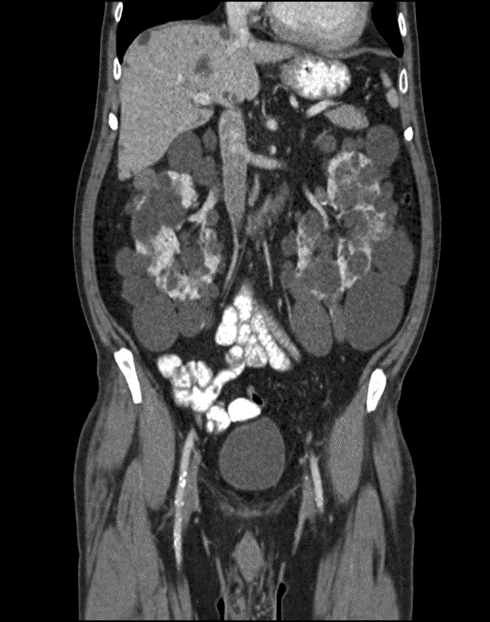

CT abdomen (with contrast; coronal plane) Both kidneys are markedly enlarged and feature multiple round-to-ovoid, hypodense lesions of various sizes compatible with cysts. Some smaller cysts are present in the liver. Contrast-enhanced renal parenchyma is seen between the cysts.

The CT features are consistent with autosomal dominant polycystic kidney disease (ADPKD).

Thus patient had a transplant.